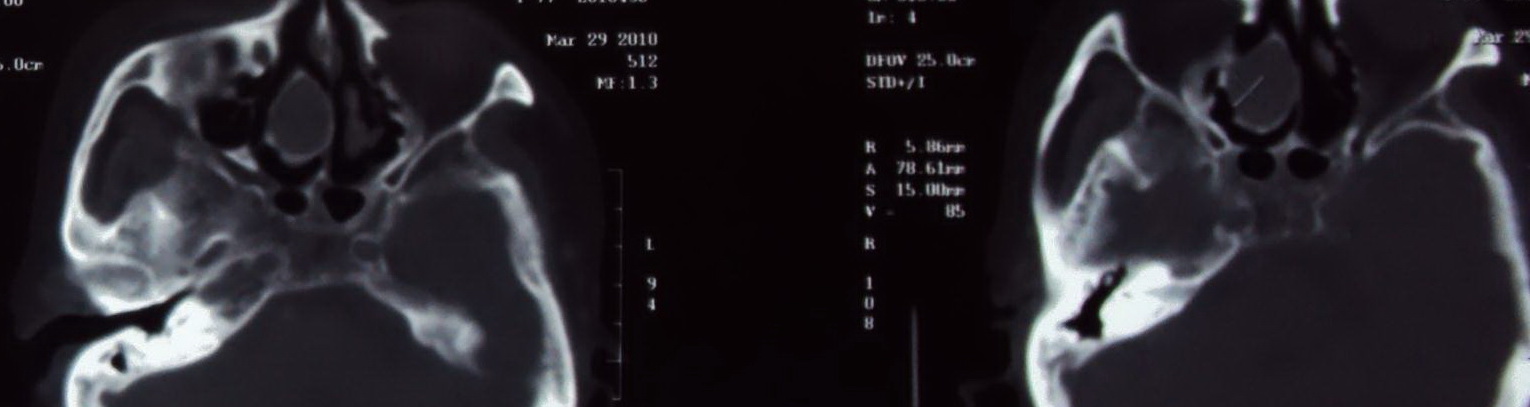

标题: CT25452:头部体检偶然发现

头部体检偶然发现 ct值73---84hu

右侧筛空窦粘液瘤

右侧筛窦粘液囊肿。